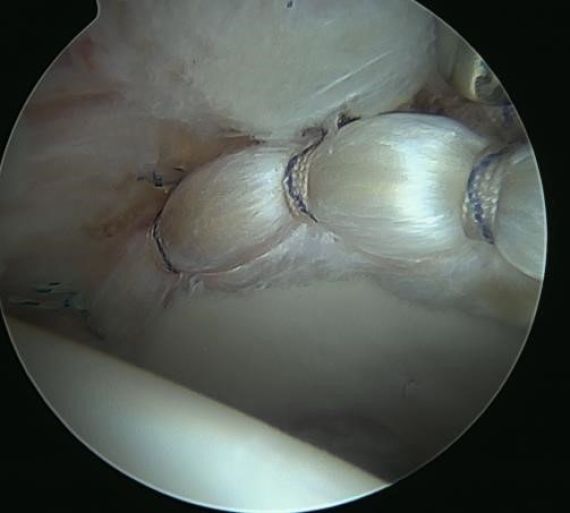

- Hip Labral Tear

Hip conditions often improve with conservative treatment including a short course of rest, anti-inflammatory pain medication, and physical therapy. An ultrasound-guided cortisone injection is sometimes necessary for patients with persistent pain. If pain continues despite conservative treatment, hip arthroscopy is an excellent treatment option for patients with labral tears, femoroacetabular impingement (FAI), tears of the gluteus medius or proximal hamstring, among other conditions.